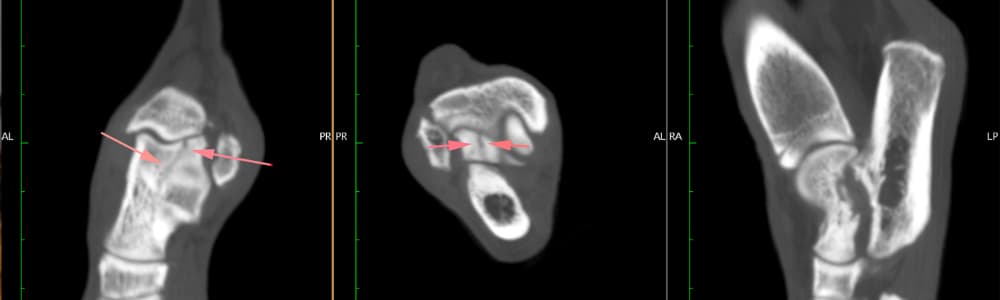

Mark Bush, RCVS Recognised Specialist in Small Animal Surgery (Orthopaedics) initially identified a swollen and painful tarsus. CT imaging uncovered rare and complex fractures — one affecting the sustentaculum tali of the calcaneus and another involving the lateral ridge of the talus, extending into the joint.

CT shows tarsus with fractures of the sustentaculum tali of the calcaneus and the lateral ridge of the talus